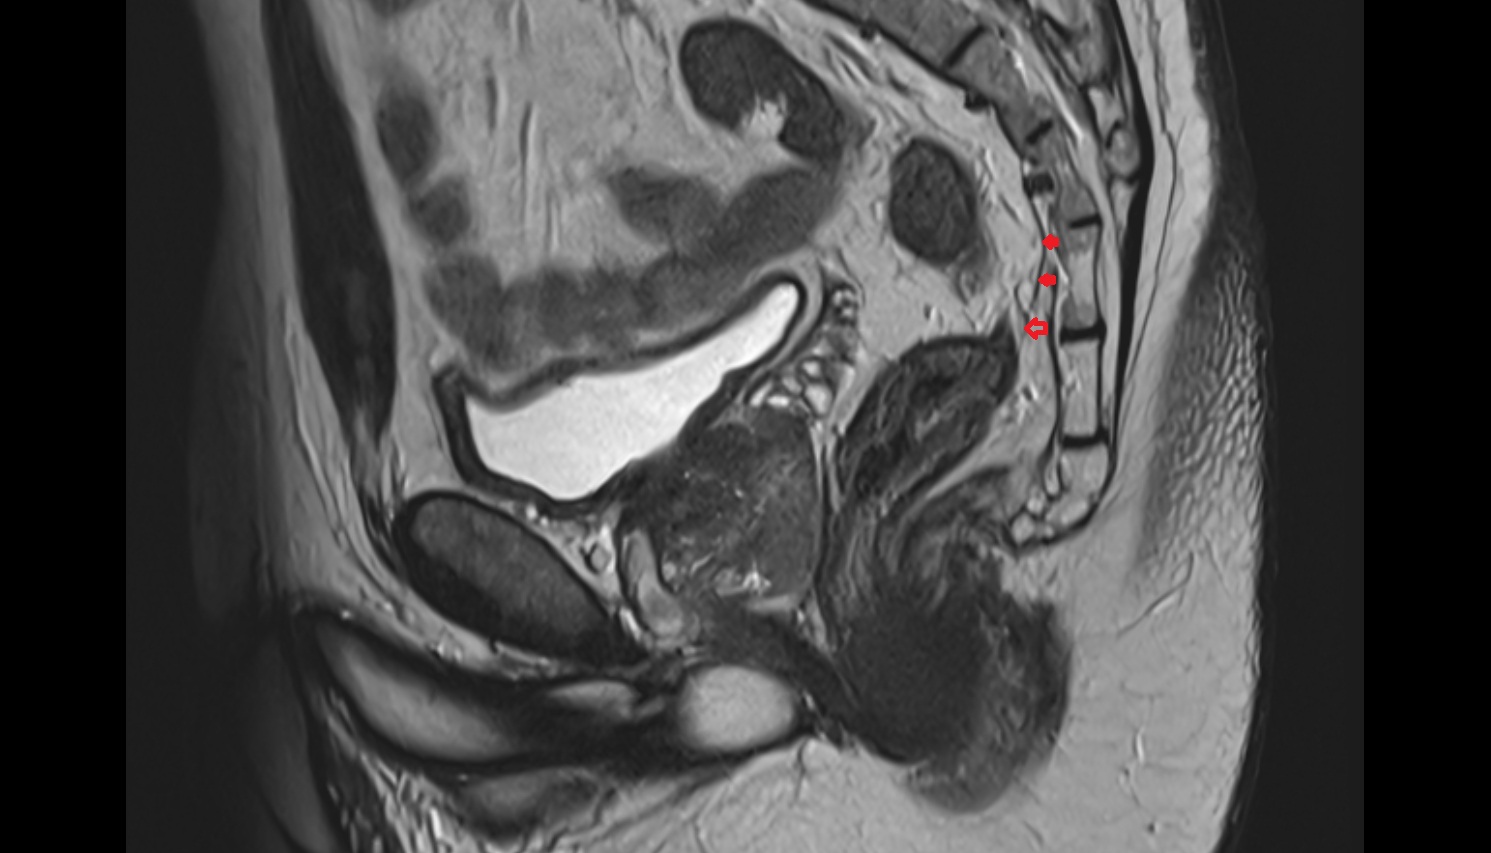

- Uterus

- Body of uterus

- Fundus of uterus

- Cervix of uterus

- Isthmus of uterus

- Vagina

- Fornix of the vagina

- Endometrium of uterus

- Myometrium of uterus

- Perimetrium of uterus

- Junctional zone of uterus

- Broad ligament of uterus

- Uterosacral ligament